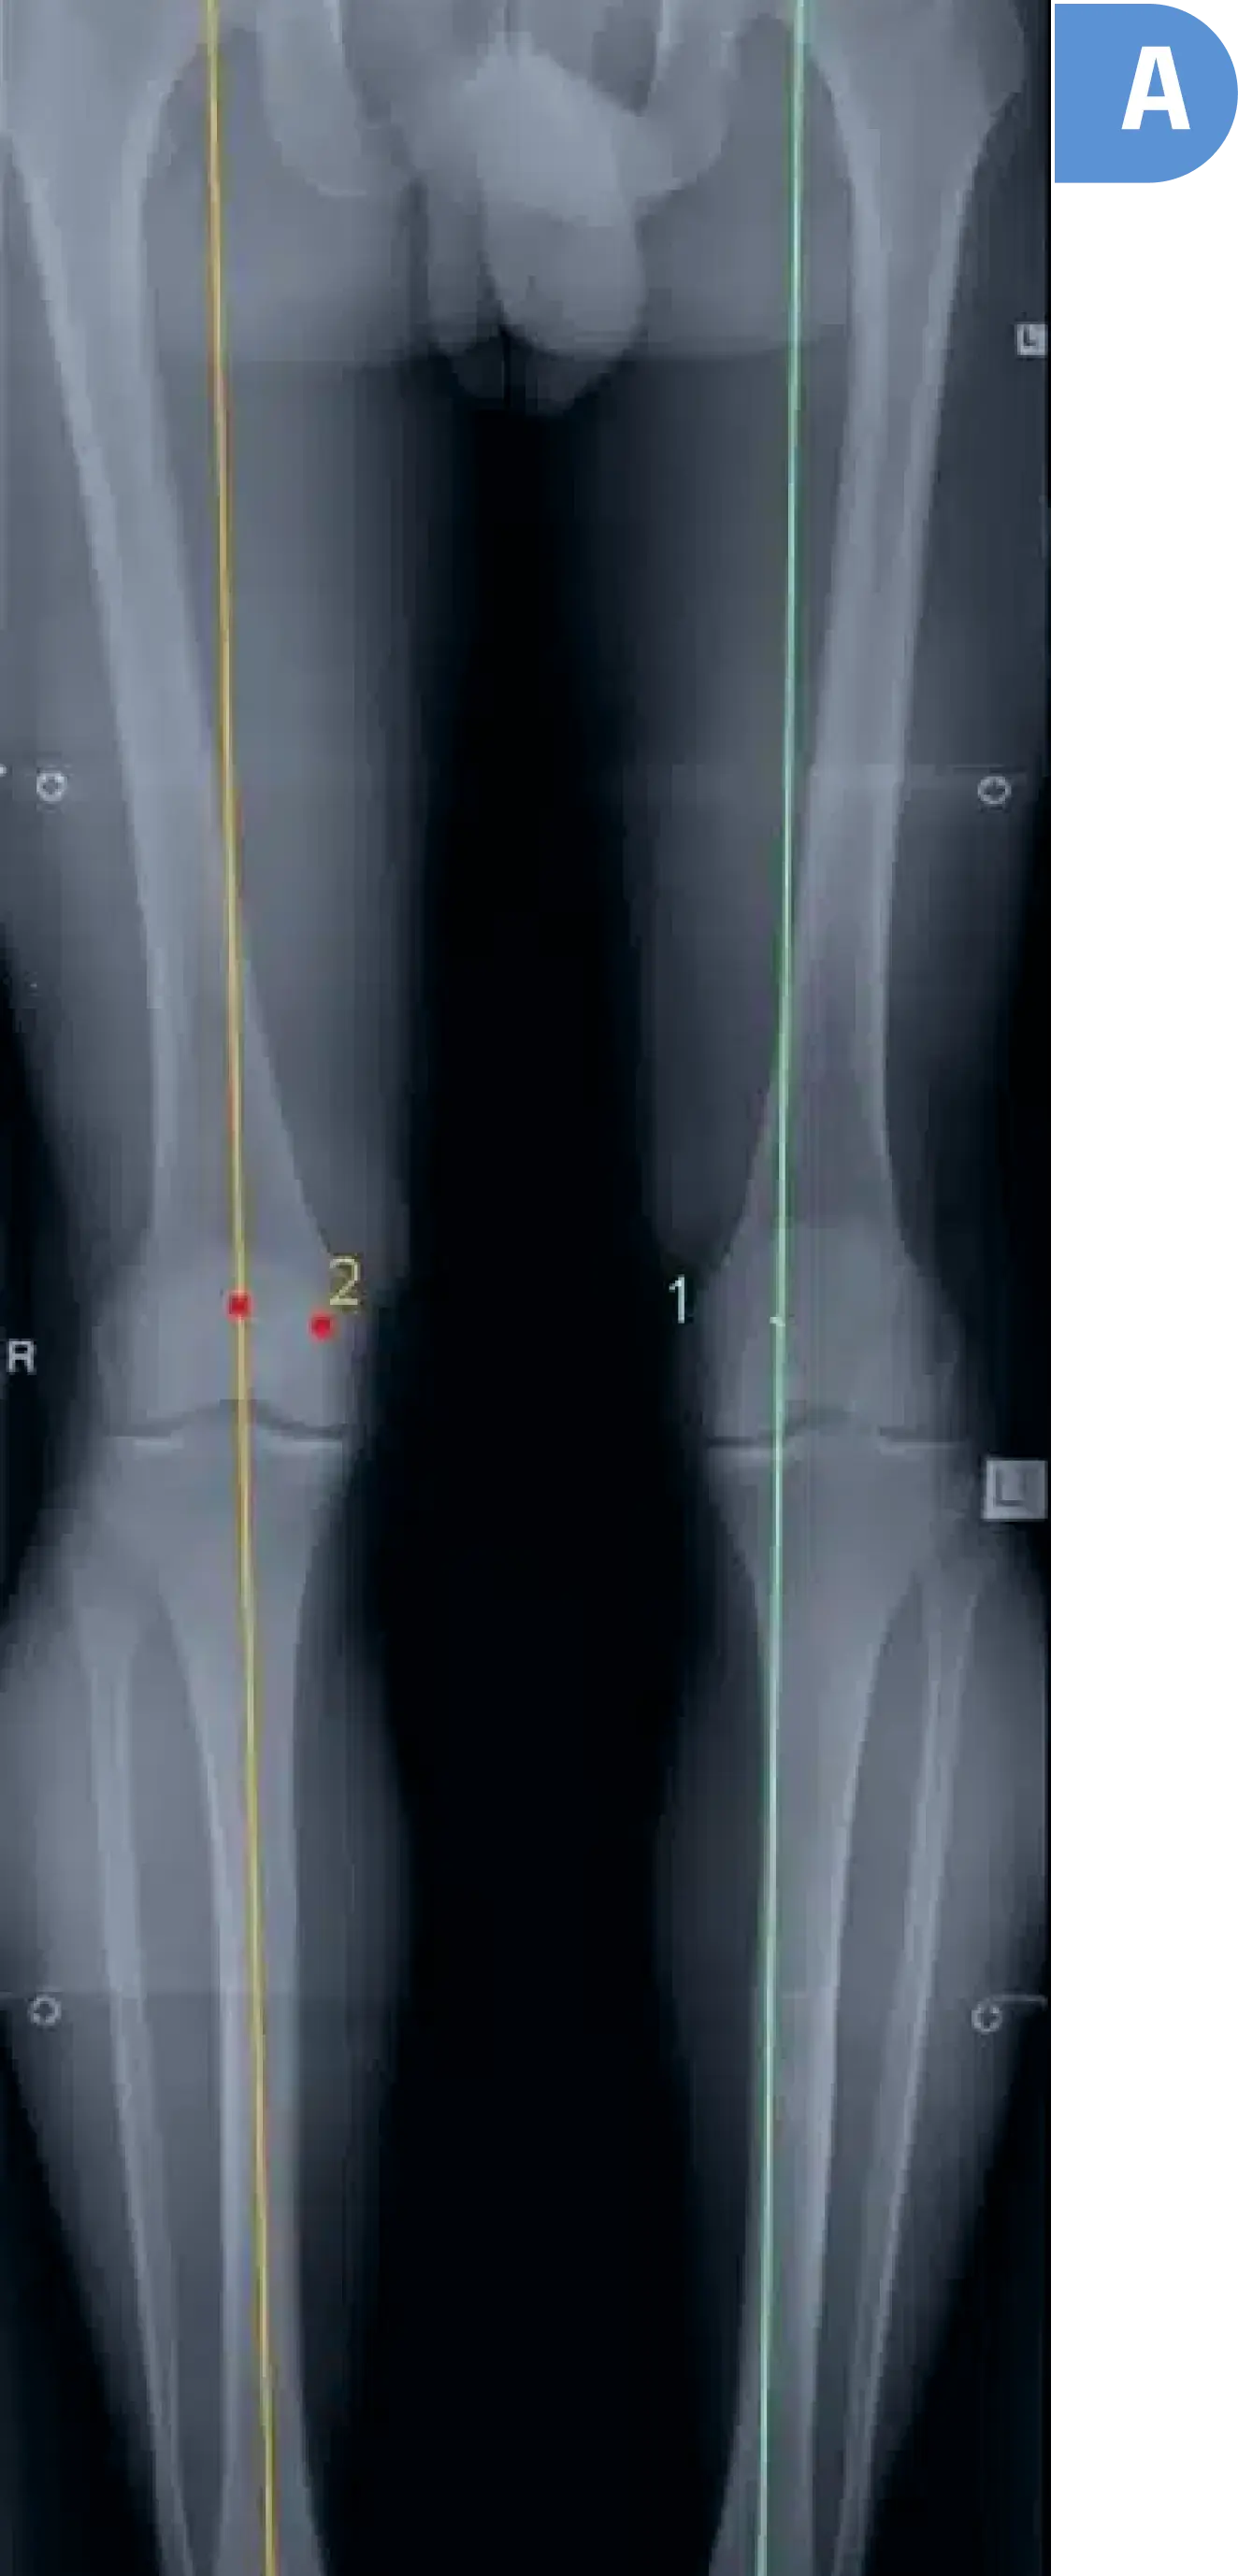

WEB限定お買い得商品の新着アイテム Knee ゼロからはじめる! Osteotomyアップデート Knee 日本 | その他

WEB限定お買い得商品の新着アイテム Knee ゼロからはじめる! Osteotomyアップデート Knee 日本 | その他

ゼロからはじめる! Knee Osteotomyアップデート | 日本 Knee。Frontiers | An algorithmic approach to soft-tissue。OsteotomyApp - Orthogate。米・雑穀・粉類 04。「ゼロからはじめる!Knee Osteotomyアップデート」\r日本Knee Osteotomyフォーラム\r定価: ¥ 11000●カバーなどの外観は、多少の使用感や擦れ、細かな傷があることがありますが、通読には問題ないと思います。Knee Osteotomy | Singapore Surgeon | Delay Joint Replacement。●あくまで中古品ですので、神経質な方はご遠慮ください。感性のバケモノになりたい 十文字美信 写真集。●本図書へのメモ、書き込みはありません。詩集/エレファントカシマシの詩。※送料込みの価格です。絶版 ノーマ 北欧料理の時間と場所 レネ・レゼピ。※即購入いただいて構いません。少女戦記(1〜12巻)。当日もしくは翌日に発送します。ユダヤ人問題とシオニズムの歴史 新版。※自宅では喫煙をしておりません。【希少】新メンズカット 本間義和 大野邦夫 安藤実 共著。動物も飼育しておりません。池田大作 写真選集 自然との対話 RENDEZVOUS WITH NATURE。※本の状態を画像でご確認、ご理解の上、ご購入をお願いいたします。重戦機エルガイム 40th オフィシャルブック。気になる箇所がありましたら、写真を追加しますのでコメントお願いします。Wiederehen Feiern1.2ポストカード付き。#日本KneeOsteotomyフォーラム #日本Knee_Osteotomyフォーラム #本 #自然/医療・薬学・健康